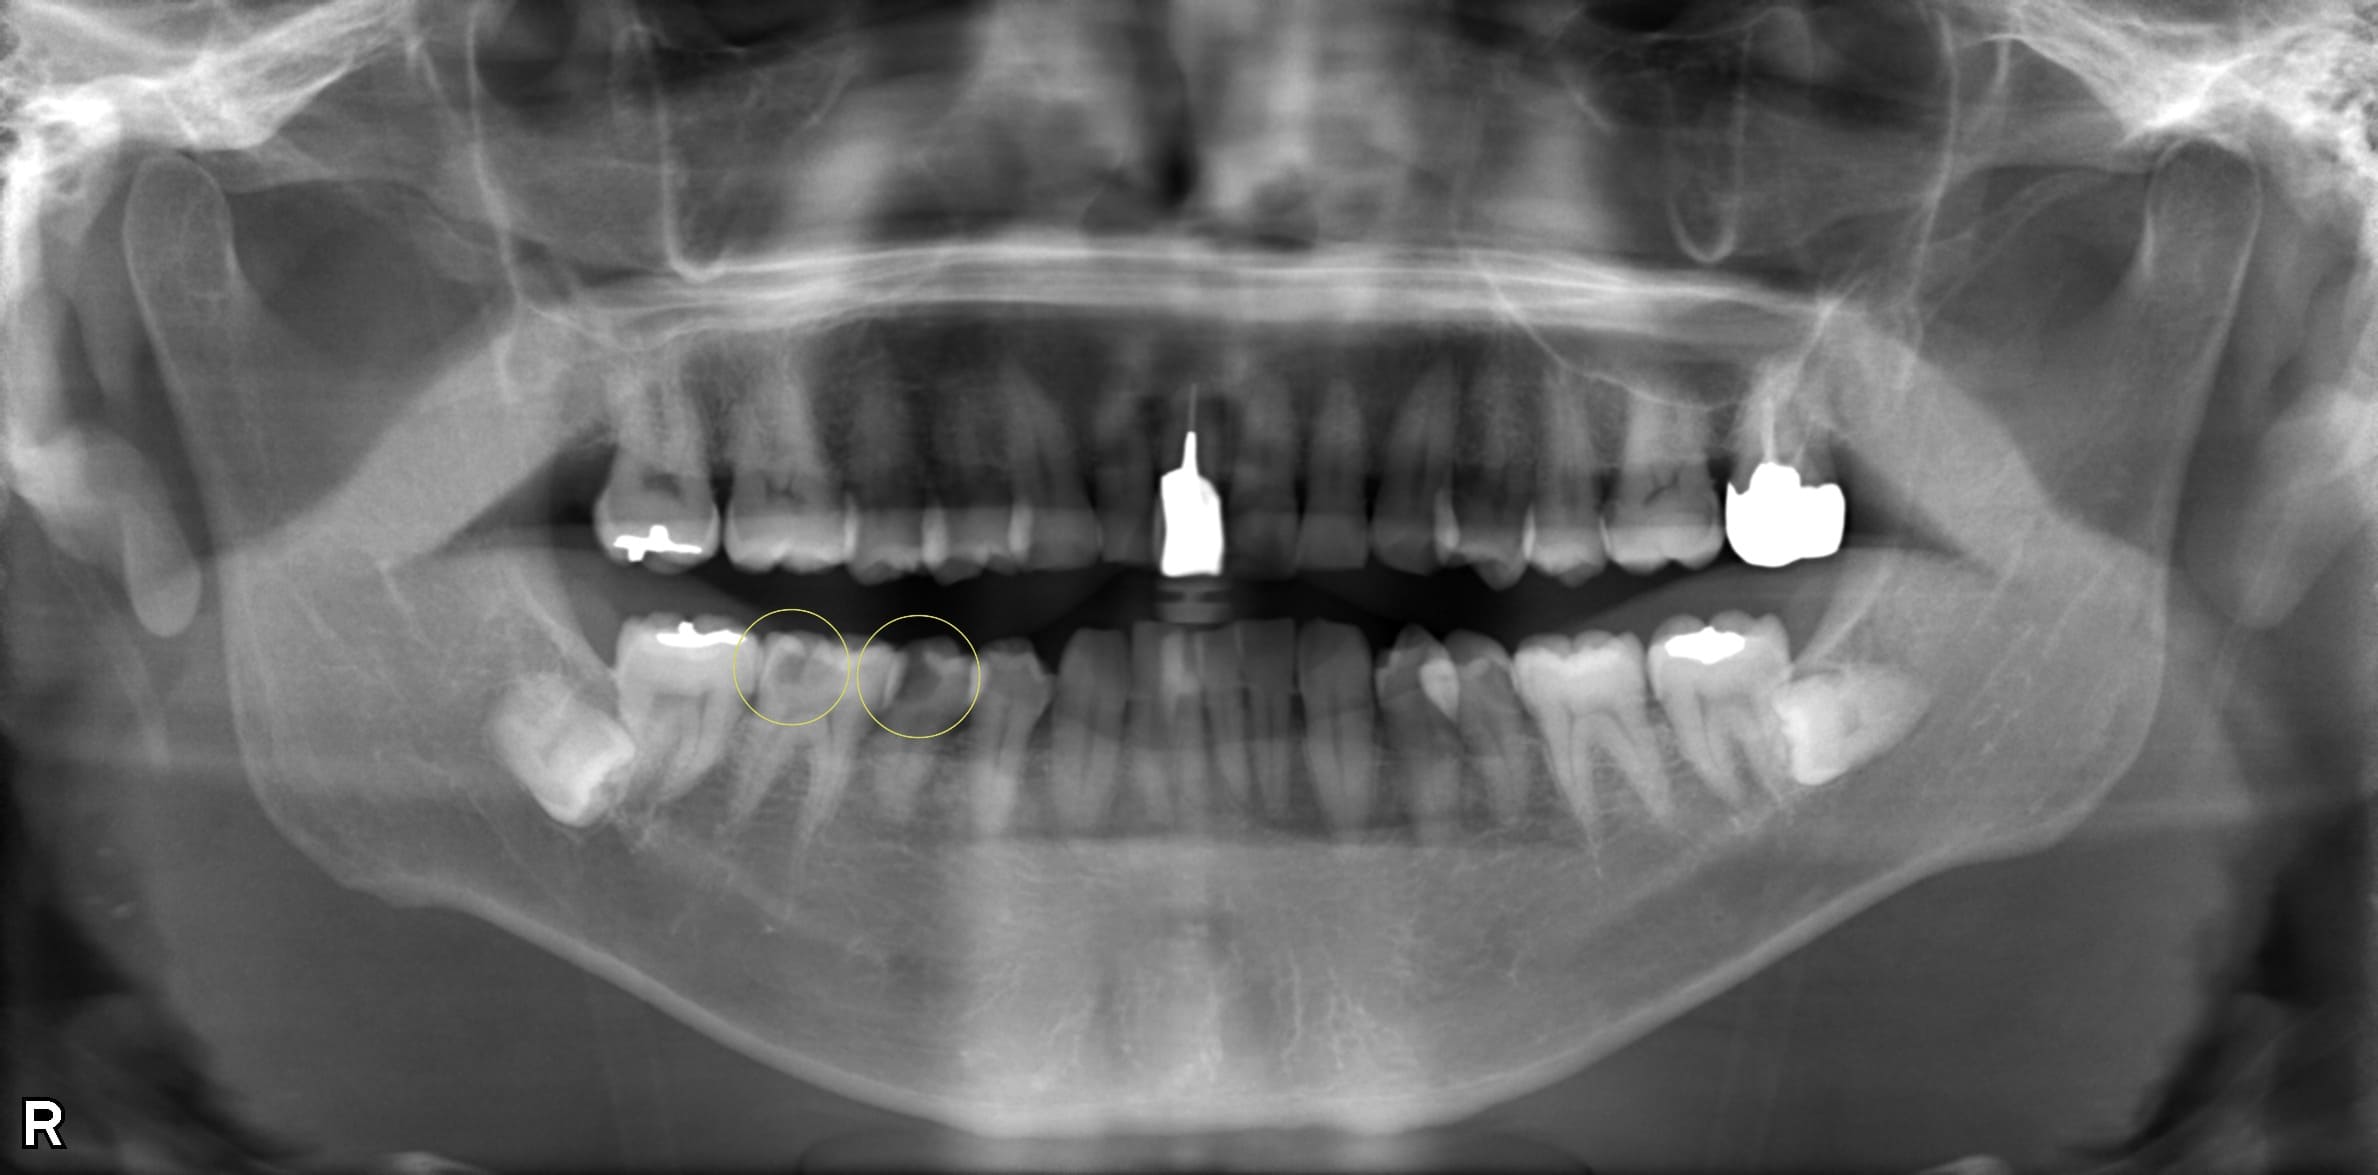

症例紹介